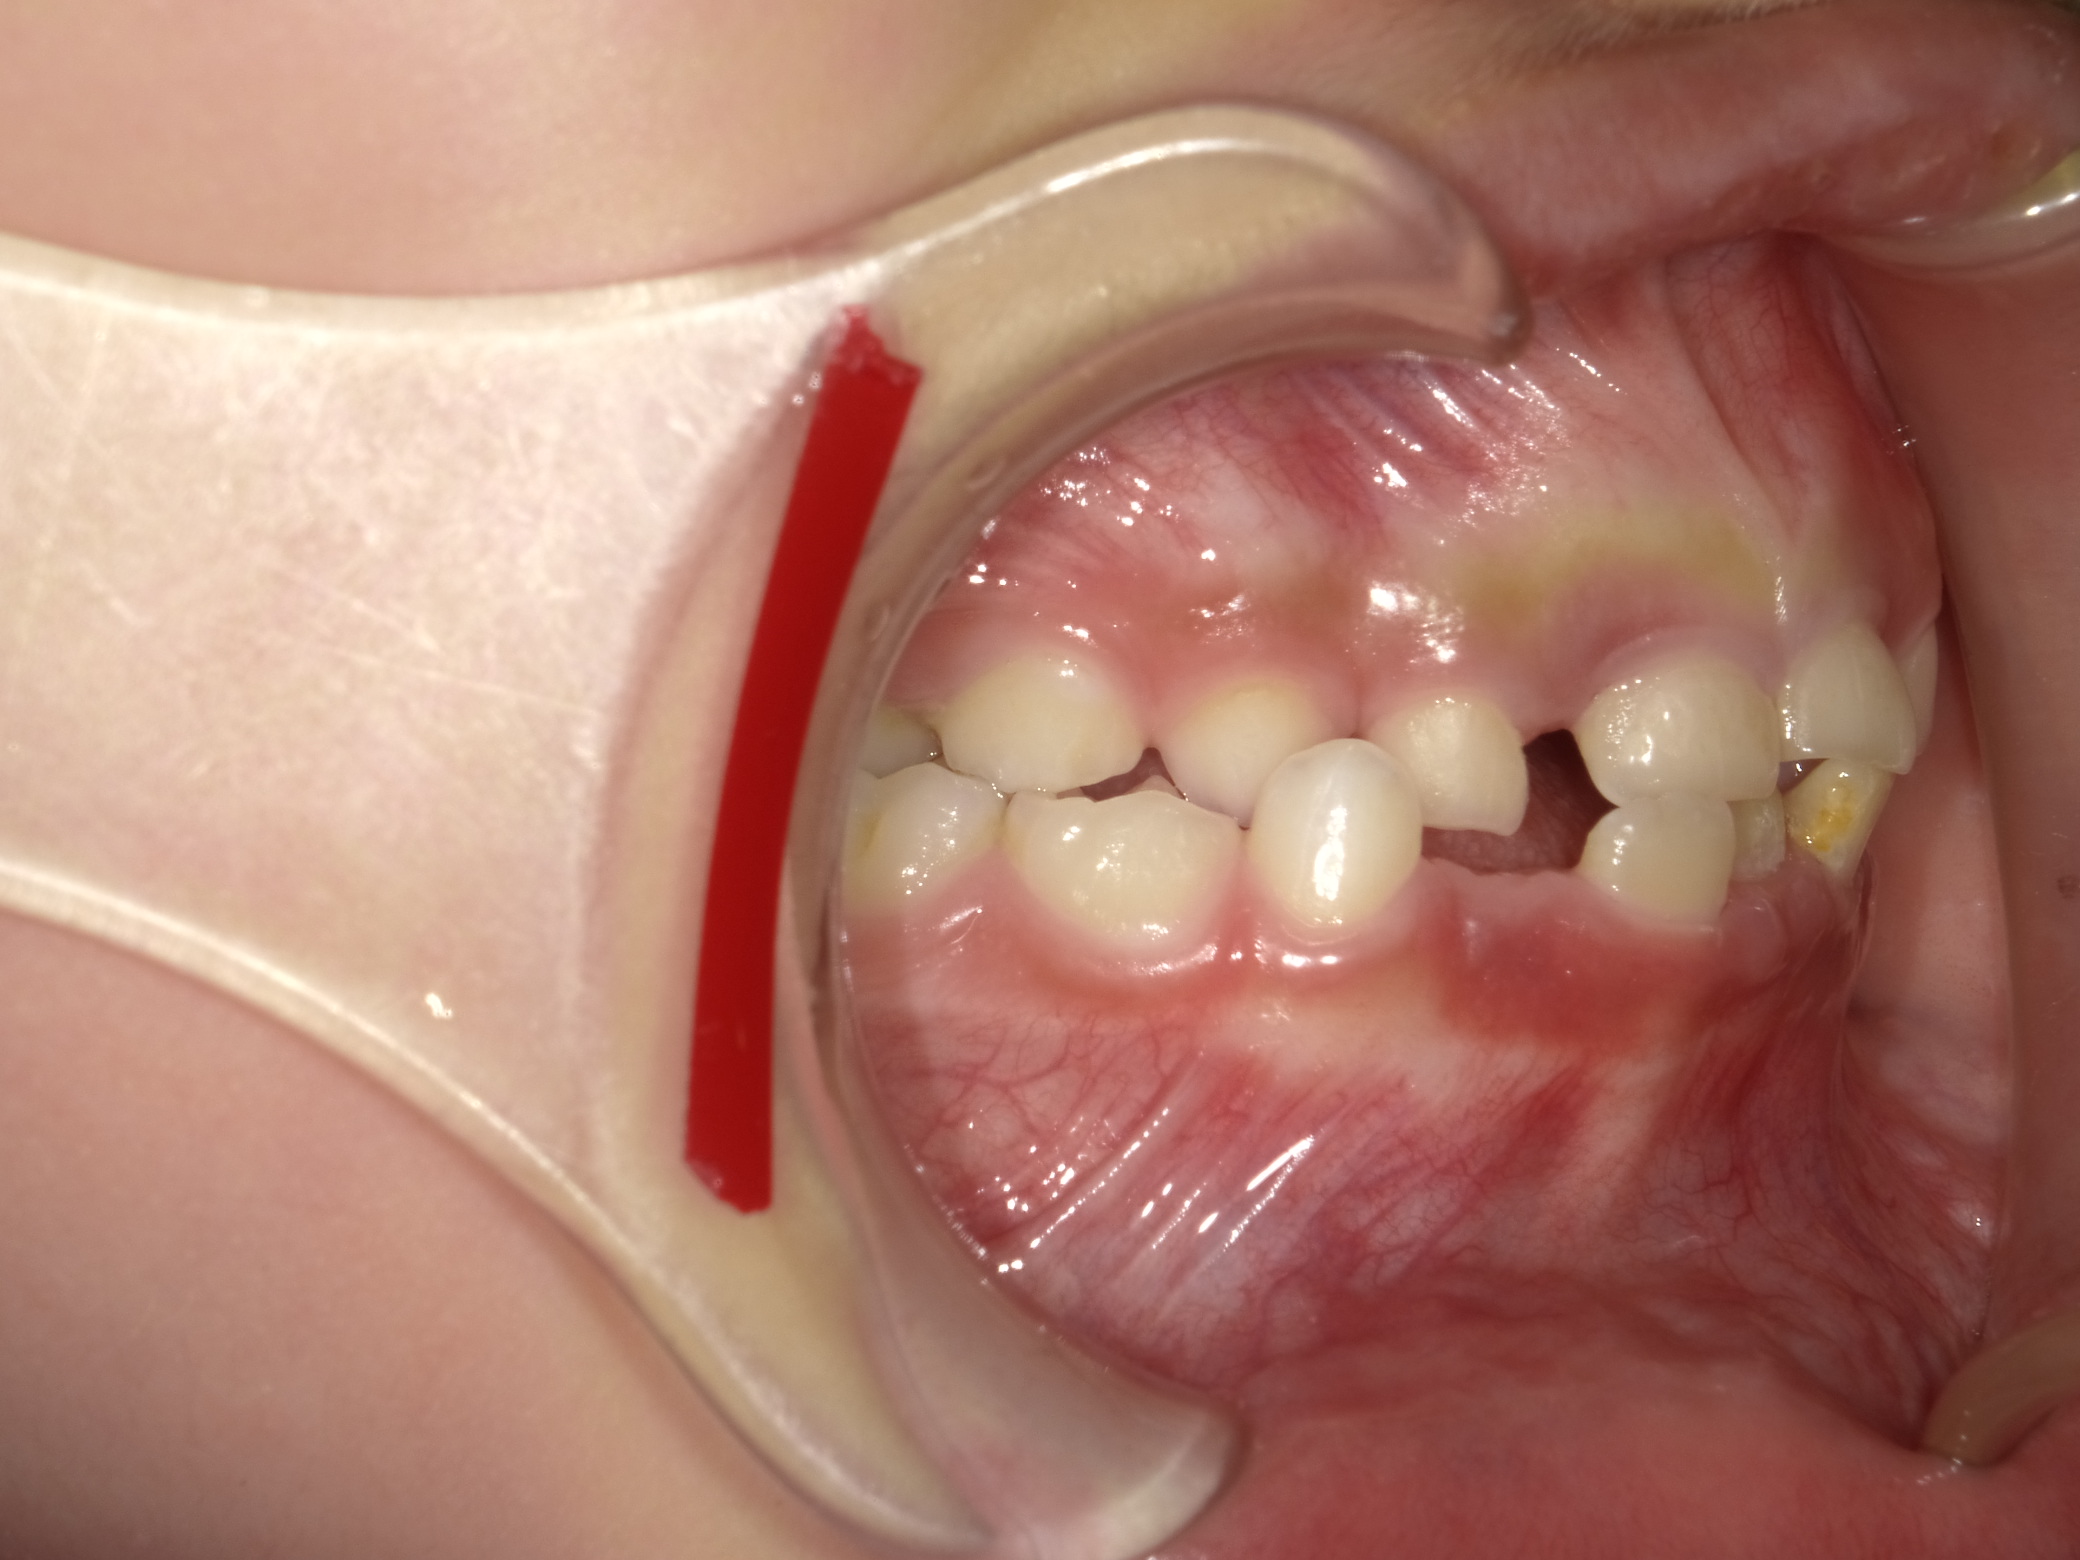

右横